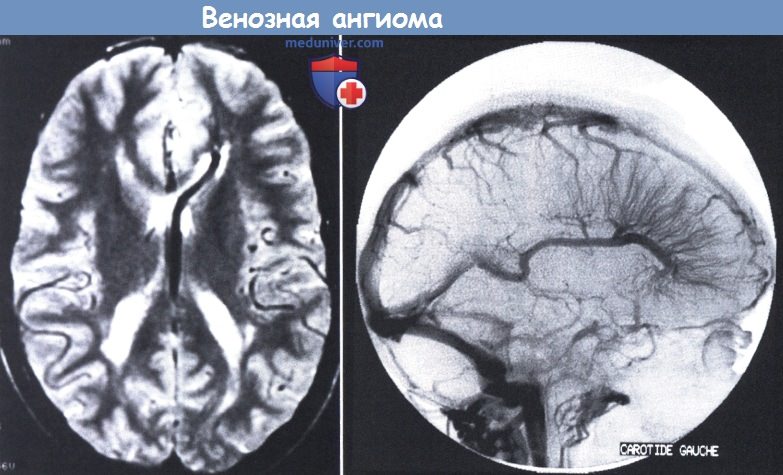

Мр картина венозной ангиомы левой гемисферы мозжечка - 96 фото